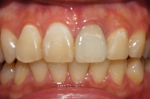

オフィスホワイトニング1日8回照射

➡

オフィスホワイトニング1日だけの症例です。

詰め物や被せ物がないのでバランス良く白くなりました。

当院のオフィスホワイトニングは薬液を使い切るまで照射回数フリーなので頑張っていただければ一日で白さを実感いただけます。